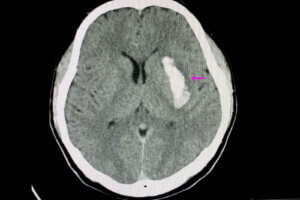

Existen 2 tipos de accidentes cerebrovasculares, 3 si hilamos muy fino: accidente cerebrovascular isquémico y accidente cerebrovascular hemorrágico, siendo esta última categoría dividida en otros 2 eventos, ACV por hemorragia intracerebral (ICH) y por hemorragia subaracnoidea. Te contamos sus particularidades.

Accidente cerebrovascular hemorrágico

El ACV hemorrágico es causante del 15 % de los derrames cerebrales totales (con un intervalo del 10-20 %). En este caso, la historia es muy distinta, pues el daño neuronal es causado por una ruptura de un vaso sanguíneo y el encharcamiento del tejido cerebral.

Los principales lugares cerebrales de sangrado son los ganglios basales (50 %), lóbulos cerebrales (20 %), tálamo (15 %), tronco encefálico (10 %) y cerebelo (10 %). Las lesiones primarias se producen cuando el hematoma generado por la ruptura del vaso provoca compresión en el tejido cerebral y causa un aumento de la presión intracraneal.